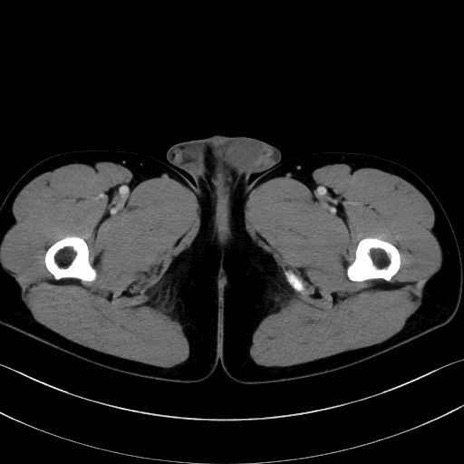

内閉鎖筋 (Obturator internus)